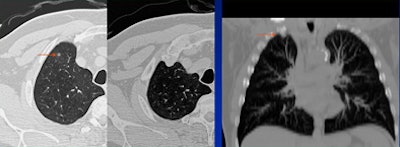

|  |

| Satisfaction of search error: The reader found the pacemaker but missed the lung mass behind it. |